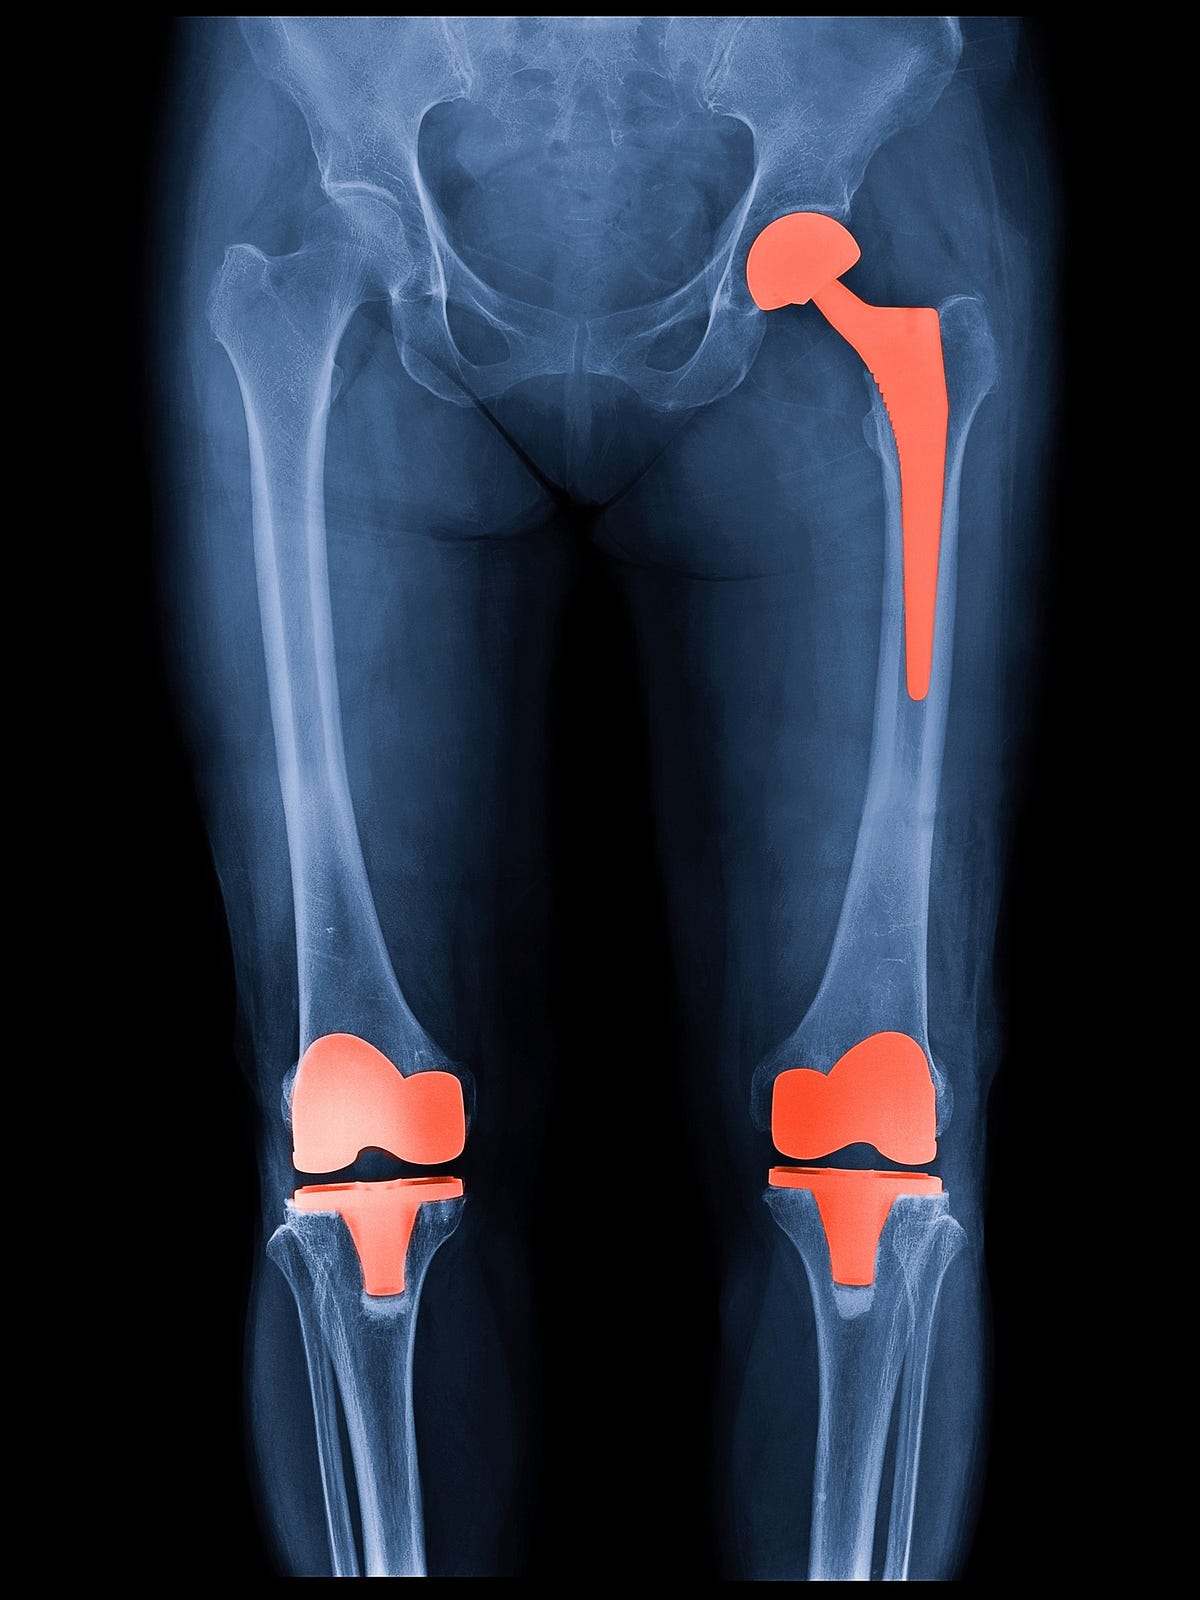

How Long Do Knee Replacements Last Today . — an aging population drives the global demand for knee replacement surgery, exceeding 1 million procedures annually. — how long does a knee replacement last? knee replacement, also called knee arthroplasty or total knee replacement, is a surgical procedure to resurface a knee damaged by arthritis. Younger patients who have a knee. how does a knee replacement last? — for people considering hip or knee replacement surgery, it's something they want — and need — to know. — for most people, knee replacement provides pain relief, improved mobility and a better quality of life. A knee replacement usually lasts a long time. In the us alone, surgeons perform. In fact, more than 90% of people who have. — according to a 2019 research review, more than 82% of total knee replacements are still functioning 25 years later. But wear and tear can. In most cases, an implant will last at least 20 years or longer.

How Long Do Knee Replacements Last Today how does a knee replacement last? — for people considering hip or knee replacement surgery, it's something they want — and need — to know. — for most people, knee replacement provides pain relief, improved mobility and a better quality of life. how does a knee replacement last? In fact, more than 90% of people who have. In most cases, an implant will last at least 20 years or longer. — according to a 2019 research review, more than 82% of total knee replacements are still functioning 25 years later. But wear and tear can. A knee replacement usually lasts a long time. knee replacement, also called knee arthroplasty or total knee replacement, is a surgical procedure to resurface a knee damaged by arthritis. — an aging population drives the global demand for knee replacement surgery, exceeding 1 million procedures annually. Younger patients who have a knee. In the us alone, surgeons perform. — how long does a knee replacement last?